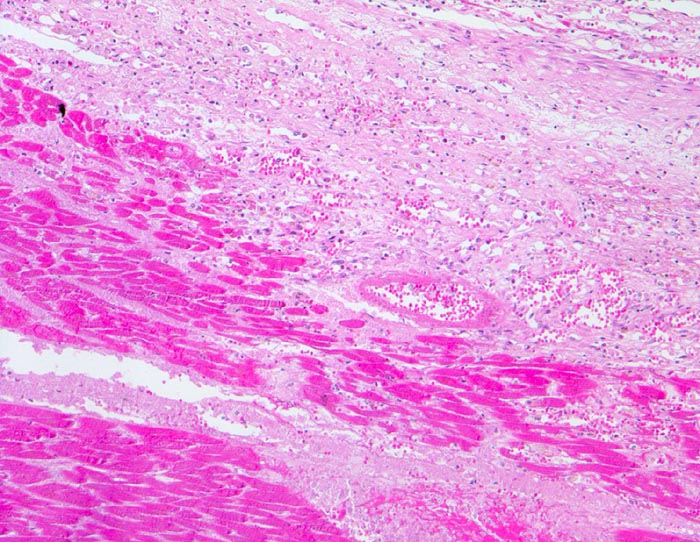

PathoPic ID 4545 - Myokardinfarkt

Myokardinfarkt

vaskulär / Durchblutungsstörung

Herz links

Kardiovaskuläres System

Hypereosinophiles Myokard (

Koagulationsnekrose) ohne erkennbare Kernfärbung. Am Rand der Nekrose Granulationsgewebe mit zahlreichen

kapillären Gefässen, Makrophagen,

bräunliche Siderophagen und Fibroblasten.

Diagnose eines Myokardinfarktes vor 4 Tagen.

Histologie

50